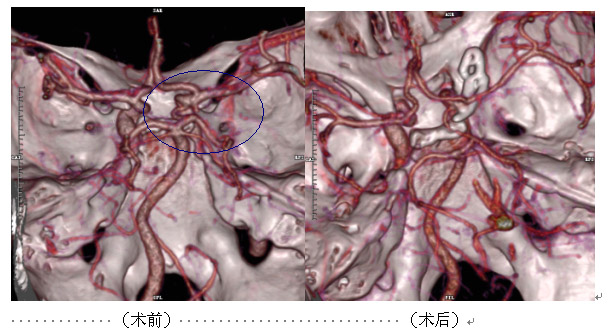

這名患者中年男性,3天前出現(xiàn)劇烈頭痛,外院頭顱CT:大腦外側(cè)裂可疑高密度影,未能確診。遂轉(zhuǎn)來(lái)我院,經(jīng)全面檢查后,明確診斷為:蛛網(wǎng)膜下腔出血。我院神經(jīng)外科進(jìn)一步行頭顱CTA檢查示:前交通動(dòng)脈囊狀動(dòng)脈瘤,證實(shí)其為出血“元兇” 。后經(jīng)手術(shù)治療,獲得康復(fù)。